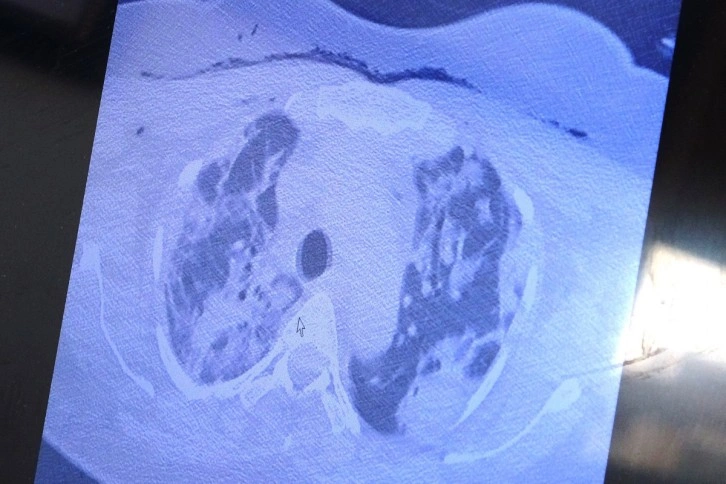

Yurt dışından kendisine gelen ve bebeği ile annesini hayata tutunmasını sağlayan Özkaya, "Bu yurt dışında hamileyken kovide yakalan ve ciddi akciğer tutulumu olan 38 yaşında hastamız var. Tedavi olmak için bizim ülkemize geldi. Ciddi solunum yetmezliği vardı. Biz hem annenin hem de bebeğin hayatını garanti altına almak için bebeği aldık. Sağlıkla doğum yaptı. Annenin akciğerine tomografi çektik. Ciddi akciğer tutulumu, ciddi harabiyet olduğunu tomografisinde gördük. Gecen yıllarda gebelerde böyle tutulumlar yoktu" ifadelerini kullandı.